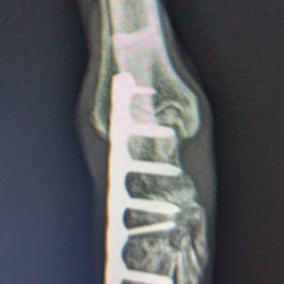

■ミニチュアダックスフント 1歳 去勢オス

前肢の成長板早期閉鎖、前肢の重度の外反変形が認められました。

関節面の変形が重度に認められます。